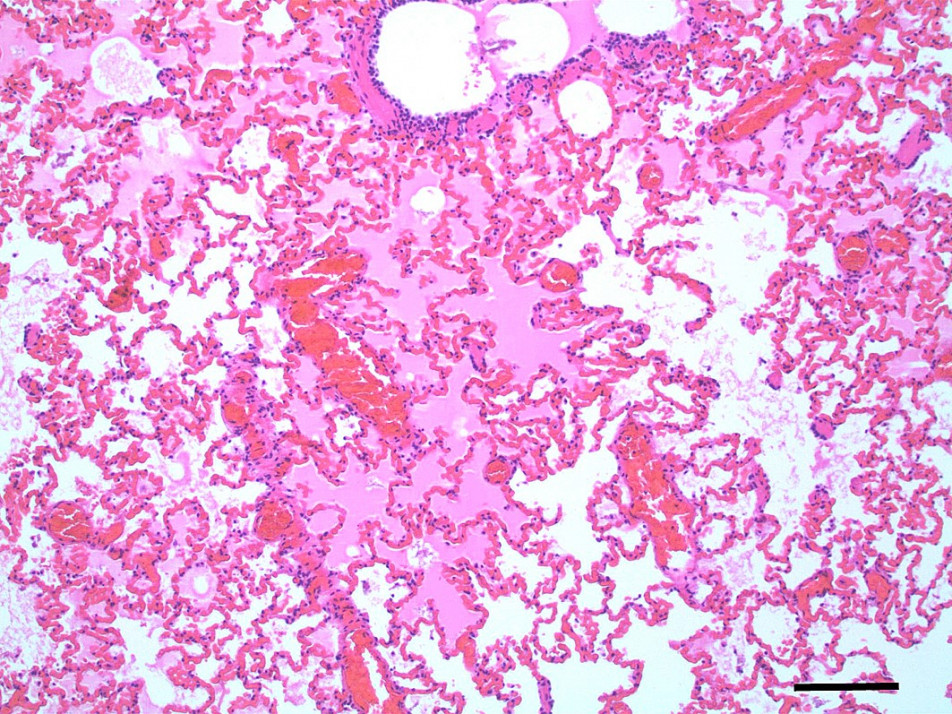

Pulmonary oedema and congestion were noted in 36% (9/25) dogs euthanised for tick paralysis and this probably contributes to the development the hypoxaemia observed in some patients (Webster et al., 2013b)(Figure 5,6). Pulmonary oedema is a consistent finding in animals affected with tick paralysis. Left lateral chest xrays of 75 dogs presenting with tick toxicity revealed that 38% had signs of pulmonary congestion manifest as pulmonary vein dilation placing them at risk of developing pulmonary oedema (Day and Schull, 2008). It is unclear what the pathophysiology of this process is but it is an ongoing area of research interest (Webster, 2014a). Treatment of pulmonary oedema with diuretics may appear logical but diuretics raise the potential for other fluid therapy complications and has not be recommended for management of pulmonary oedema from tick paralysis (Webster, 2014b). The investigation of cardiac biomarkers in dogs with tick paralysis provides further evidence that the pulmonary oedema is non-cardiac in origin (Nicolson et al., 2016).